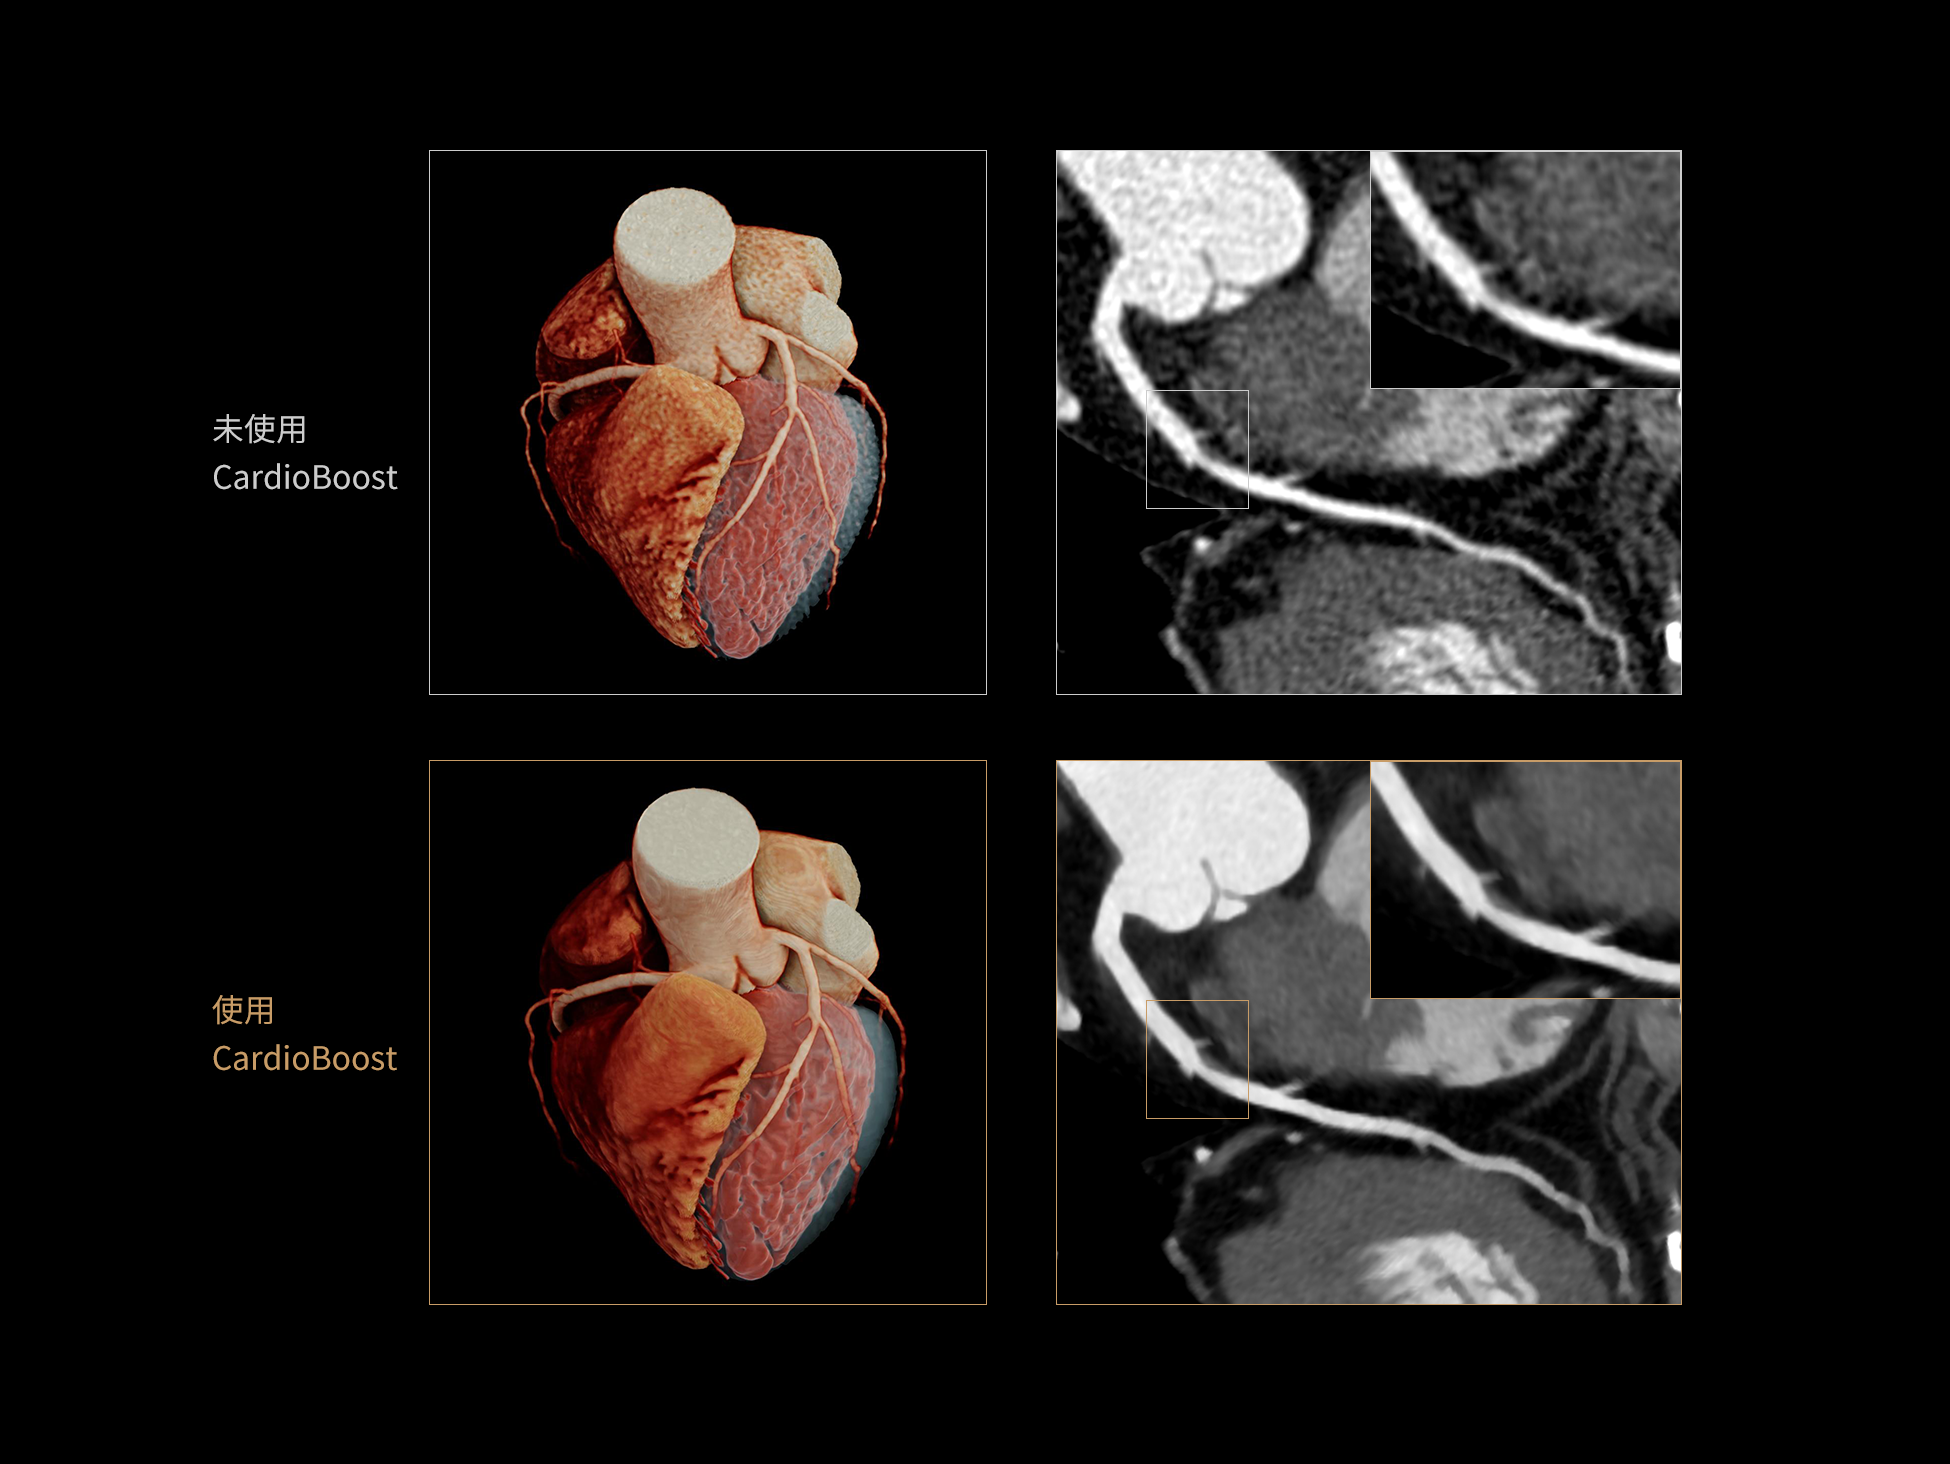

CardioBoost:专属网络设计,重塑心脏影像表现

目前心脏的 CT 检查还存在辐射剂量偏高、空间分辨率不足、 致密钙化伪影影响冠脉狭窄程度评估等方面的限 制[1][2]。CardioBoost 技术专为心脏 CT 高清成像而开发,通过 3D 神经网络的深度学习技术,利用先进的注意力机制在识别关键成像特征方面的出色表现,能够精确地聚焦于斑块、支架以及微小血管等关键细节,清晰展示这些结构与冠脉血管的边界,从而显著提高诊断的准确性,并提升医生的诊断信心。创新的 CardioBoost 心脏图像重建算法,不仅实现了图像清晰度的提升和伪影的去除,更能在减少辐射剂量的同时,保证心脏图像的高质量和图像纹理的自然。

CardioBoost核心创新

采用 3D 神经网络的空间结构优势与精细的组织分类能力,CardioBoost 技术优化了组织对比,高清展示血管斑块,使斑块与血管边缘的轮廓清晰可辨,提升斑块诊断与评估的精确性。

借助 3D 神经网络设计、空间注意力机制聚焦与特征强化作用,CardioBoost技术提升图像的空间分辨率,实现冠脉支架的高清成像,对支架形态与管腔通畅度的评估更精准。

CardioBoost 整合先进的 3D 神经网络和空间注意力机制,大幅增强数据处理的速度与精确度。该技术能有效抑制由致密钙化引起的晕状伪影,清晰展现钙化斑块的原始结构和大小,对冠脉狭窄的评估更加精确可靠。

对比度强化模块

分辨率强化模块

伪影抑制模块